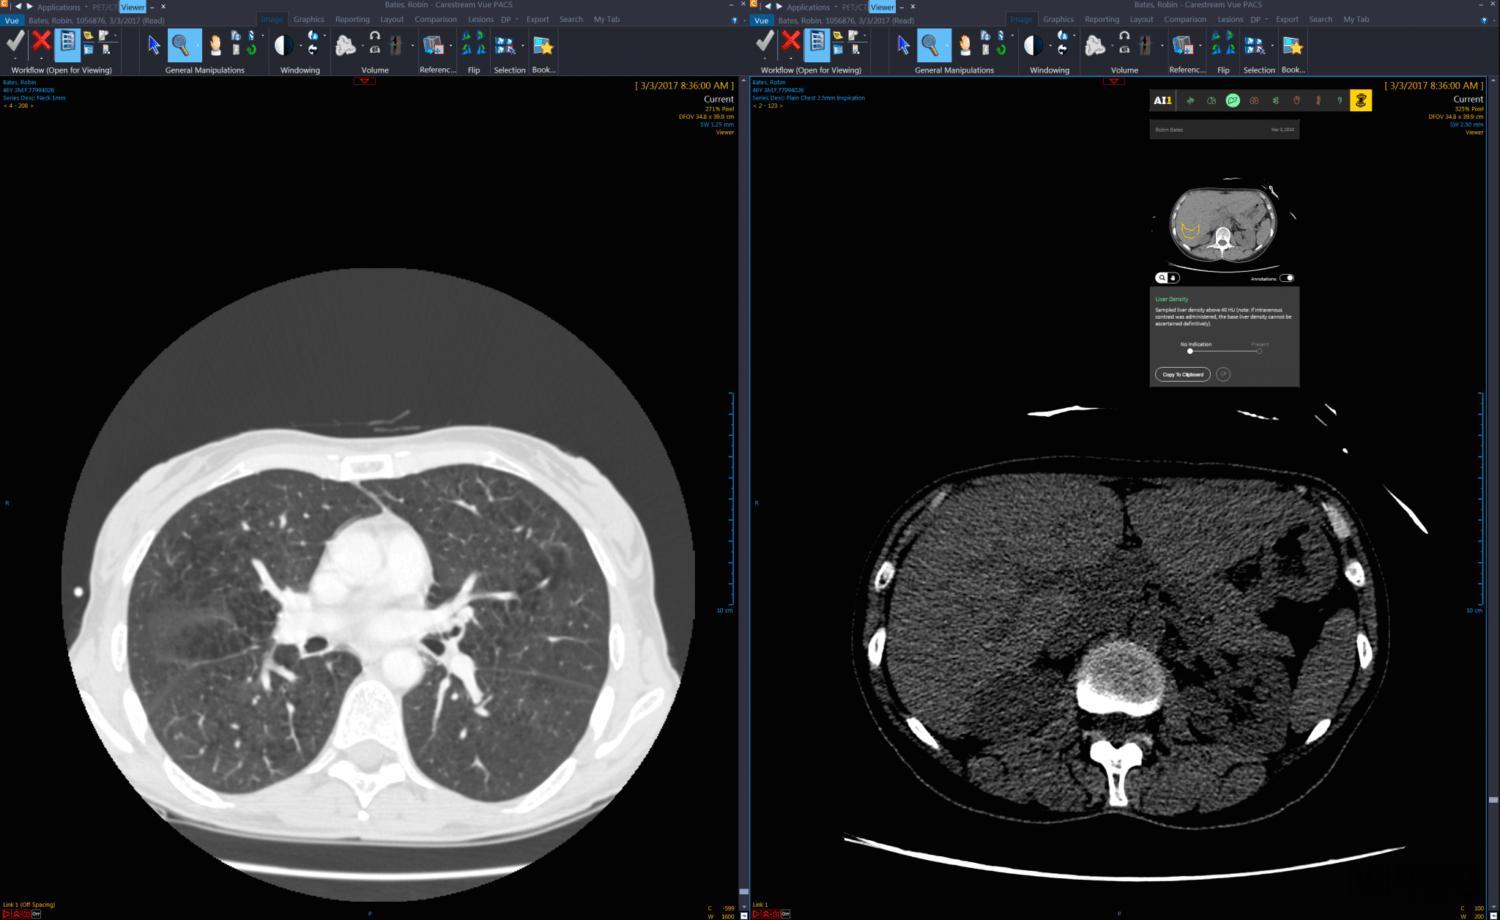

2、医疗成像

2017年2月,基于云的医学影像管理公司Ambra Health宣布推出面向医学影像的云开发平台Ambra for Developers。这是全球第一个专为医学成像设计的云开发平台。

通过新的API,医疗系统和医院的IT部门可以轻松地将图像扩展到其他应用程序中,如人口健康、报表工具等。此外,第三方开发商可以迅速将Ambra成像技术整合为医疗应用的一部分,为用户提供更好的患者护理。

许多具有前瞻性思维的公司正在利用Ambra的云开发平台来改进其解决方案。包括深度学习、诊断决策、远程放疗、专业图像分析等方面。Ambra for Developers令合作伙伴将一流的成像管理方案与应用程序构架无缝整合起来。

Ambra Health已连续三年被KLAS 评为医学影像交换解决方案的领导者。如今,有超过750家医疗服务提供商使用Ambra网络共享图像,每个月,全球50多个国家和地区的用户登录平台,登陆次数超过75万次,同比增长达500%。

同样是在医学影像方面,2017年11月,深度学习影像分析公司Zebra Medical Vision宣布,该公司所有已发布和未发布的放射算法将在Google Cloud上启用。

作为医疗影像仪器和深度学习领域的先驱者,Zebra-Med正在推动其商业模式的透明化,以促进健康产品在全球的推广应用。

根据IDC 2017年的健康观察数据,全球每年新增超过450 PB的图像数据,图像存储量预计将在未来5年翻一番,这对卫生保健提供商追踪其存储和IT基础架构的扩展方面提出了挑战,同时也带来了机会。